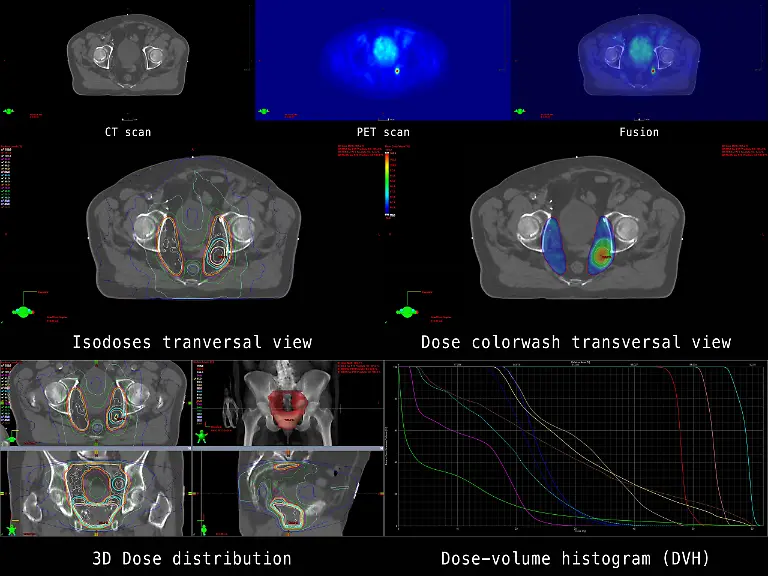

Er war ein Revolutionär der Medizintechnik: Der Physiker Wilhelm Conrad Röntgen entdeckte 1895 zufällig die X-Strahlen, was nicht nur für die Diagnostik in der Medizin ein Meilenstein war. Später wurden die Strahlen und das Verfahren nach ihm benannt. Röntgen starb vor 100 Jahren in München.